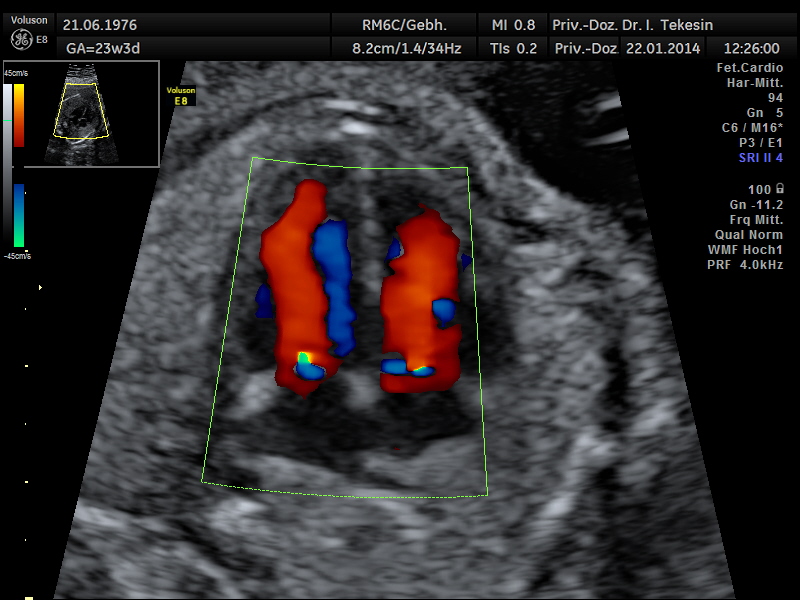

Fetale Echokardiographie

Ein weiterer Bestandteil der weiterführenden Ultraschall-Diagnostik ist die Beurteilung des kindlichen Herzens und der großen Blutgefäße, die fetale Echokardiographie. Dabei untersuchen wir die Lage, Größe und Symmetrie des Herzens, Anatomie der Herzstrukturen, Funktion der Herzklappen, Herzfrequenz und die Lage der großen Gefäße. Mit Hilfe der farbkodierten Doppler-Sonographie des Herzens werden weitere Details untersucht: die Funktion der Herzkammern, Herzscheidewände, Blutflüsse im Herzen und Blutflüsse in den großen Gefäßen.

Dopplersonographie

Auch das Durchblutungsverhalten in der Nabelschur und in den Gebärmuttergefäßen wird mit Hilfe des Doppler-Ultraschalls dargestellt. Diese Untersuchung ist eine ergänzende Untersuchung im Rahmen der US-Feindiagnostik und ermöglicht eine Beurteilung des Blutflusses in den kindlichen und mütterlichen Gefäßen mittels einer speziellen Technik. Bei dieser Untersuchung wird die Blutströmung farbig und akustisch dargestellt. Die Geräusche, die man während der Untersuchung hören kann, entstehen durch technische Effekte (Doppler-Effekt), welche der Untersucher und die werdende Eltern hören können, jedoch nicht das ungeborene Kind.

Durch Darstellung der Blutflussmuster in den mütterlichen Gefäßen (Arterie uterina rechts und links) zwischen der 20.-25. SSW können Feten mit dem Risiko einer späteren Mangelversorgung (Plazentainsuffizienz) entdeckt und somit im weiteren Schwangerschaftsverlauf optimal überwacht werden. Ein erhöhtes Risiko für die Entwicklung einer Präeklampsie (mütterlicher Bluthochdruck und Eiweißausscheidung im Urin) kann ebenso festgestellt werden.

Die Beurteilung des Blutflusses in den kindlichen Gefäßen (Nabelschnurarterie [A. umbilicalis], A. cerebri media und Ductus venosus) ermöglicht eine Aussage zur Versorgung des ungeborenen Kindes. Die Doppleruntersuchung kann in unterschiedlichen Zeitpunkten der Schwangerschaft durchgeführt werden.

Normaler Vierkammer–Blick mit Farbe

Normaler Vierkammer-Blick mit Farbe